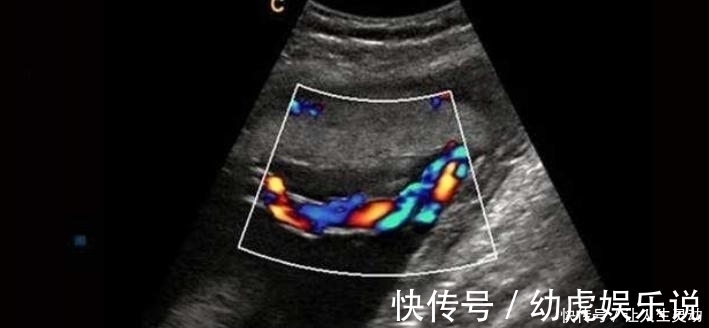

通过B超也能发现胎儿脐带扭转异常,从B超影像上能清晰地看见

文章插图